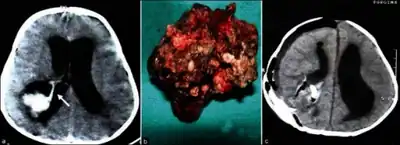

Choroid plexus papilloma occurs in the lateral ventricles of children and in the fourth ventricle of adults. This is unlike most other pediatric tumors and adult tumors, in which the locations of the tumors is reversed. In children, brain tumors are usually found in the infratentorial region and in adults, brain tumors are usually found in the supratentorial space. The relationship is reversed for choroid plexus papillomas.

Diagnosis

In terms of the diagnosis for Choroid plexus papilloma we find the following:[3]

- MRI

- Neuropathology (tumor tissue)